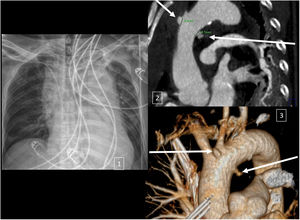

Varón de 50 años sin antecedentes, que es atendido extrahospitalariamente tras agresión con arma blanca a nivel de escotadura esternal requiriendo intubación prehospitalaria por agitación. Tras ello, es atendido en UCI en donde se aprecia deterioro hemodinámico y necesidad de activar protocolo de hemorragia masiva. Se realiza: radiografía de tórax que demuestra ensanchamiento mediastínico sugerente de lesión aórtica (fig. 1.1), ecografía con protocolo e-FAST que demuestra hemotórax izquierdo con colocación de drenaje torácico. Tras estabilización es trasladado a TC en donde se objetiva: lesión transfixiva en arco aórtico con pseudoaneurismas: entrada en cara superior y salida en zona posteriomedial (señalados con flechas blancas en las figuras 1.2 y 1.3). Con estos hallazgos se realiza intervención emergente consistente en sutura de herida superior aórtica. La evolución en UCI y planta fue satisfactoria.